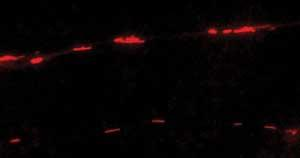

Trimmer and her colleagues use images from three-minute movies to calculate the velocity of mitochondrial movement in each Parkinson’s disease or control cybrid line with and without exposure to the low level 810 nm laser. Measuring 0.5 microns wide, the mitochondria vary in length and in terms of movement pattern; some move quickly, some jiggle back and forth in place, and some are immobile.